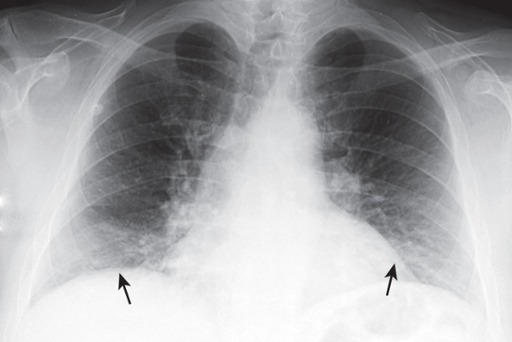

Poor Inspiration

Only eight posterior ribs are visible on this frontal chest radiograph.

A poor inspiration may “crowd” and therefore accentuate the lung markings at the bases (black arrows) and may make the heart seem larger than it actually is.